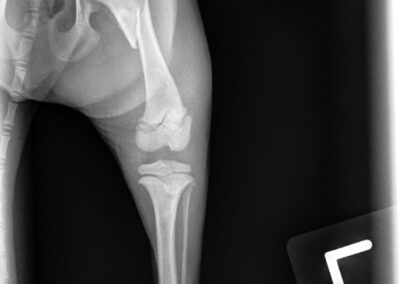

Fracture Repair

We provide surgical fracture repair for many types of broken bones. Treatment plans are individualized based on the location and complexity of the fracture, your pet’s age and size, and overall health.

Femur Fracture Before

Femur Fracture After #1

Femur Fracture After #2